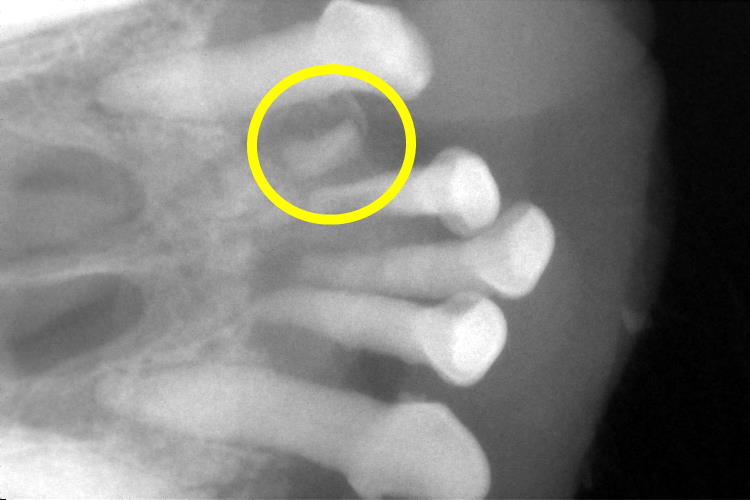

また〇印の部分は、歯根だけが残っていることが分かりました。

上の〇印の部分は吸収病巣が起こっていました。